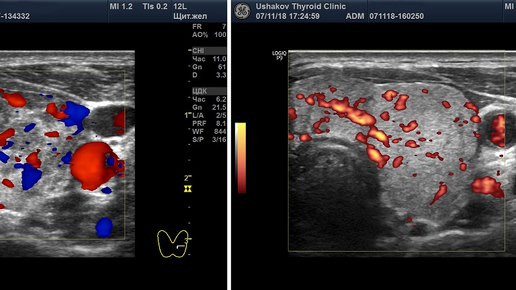

Во время УЗИ щитовидной железы врач обязан провести допплерографическое исследование каждой доли и перешейка, а также определить скорость кровотока в сосудах железы. Это исследование врачи обозначают аббревиатурой ЦДК или ЭДК (ЭД). ЦДК - цветовое допплеровское картирование, ЭДК - энергетическое допплеровское картирование (иногда применяют краткое обозначение - ЭД). ЭДК более точно, без искажений, позволяет определять кровоток. Следует знать, что допплеровское исследование щитовидной железы является обязательной, важной частью при УЗИ...

ЦДК — аббревиатура расшифровывается как «цветовое дуплексное картирование. Это та же диагностика, что и ультразвуковая допплерография, но работающая в третьем цветовом режиме. Ультразвук фиксирует изображения в режиме реального времени. Кровоток и скорость кодируются различными цветами, что позволяет врачу-диагносту поставить диагноз с высокой точностью. Дуплексное сканирование сосудов ног следует проходить людям с хроническими заболеваниями...